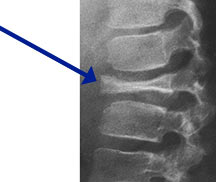

Hand-Schuller-Christian Disease

Triad:

- Destructive skeletal lesions

- Exophthalmos

- Diabetes Insipidus

- 10% of patients with unifocal EG develop multifocal and extraskeletal disease

- Usually <5 years old

- Hepatosplenomegaly, adenopathy, anemia, fever, neurological complaints

- Fatal in 15%

- Any bone but 90% have skull involvement

- Vertebral plana is braced and observed